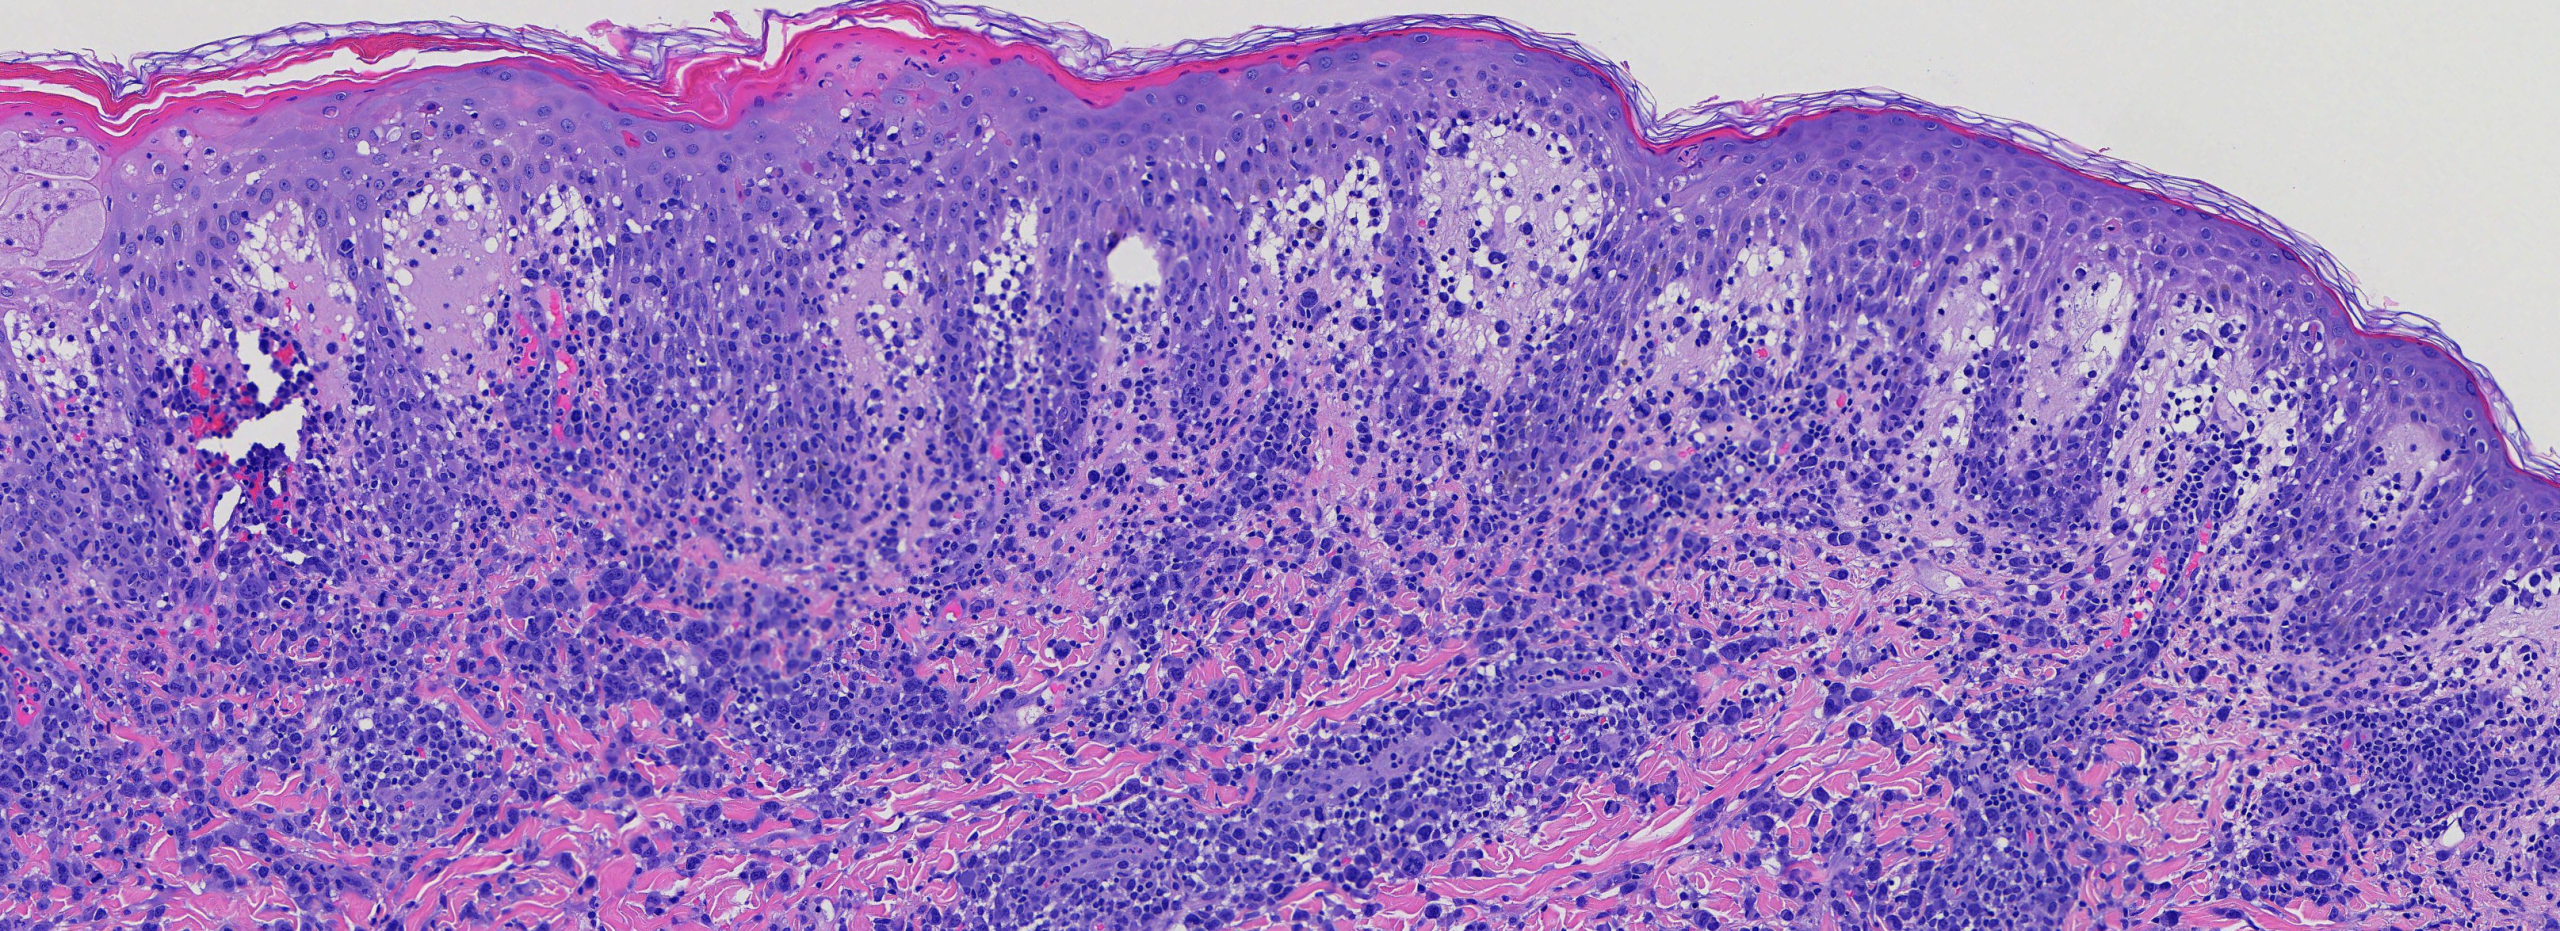

(Image 2: Medium power showing perivascular and interstitial infiltrate of mononuclear cells)

The combination of large atypical CD30+ mononuclear cells with pleomorphic hyperchromatic nuclei, set within a mixed inflammatory perivascular infiltrate, coupled with a clinical history of recurrent self-healing papulonodular lesions that wax and wane over months to years, is diagnostic of Lymphomatoid Papulosis. Critically, this diagnosis cannot be made on pathology alone — clinicopathologic correlation is paramount.